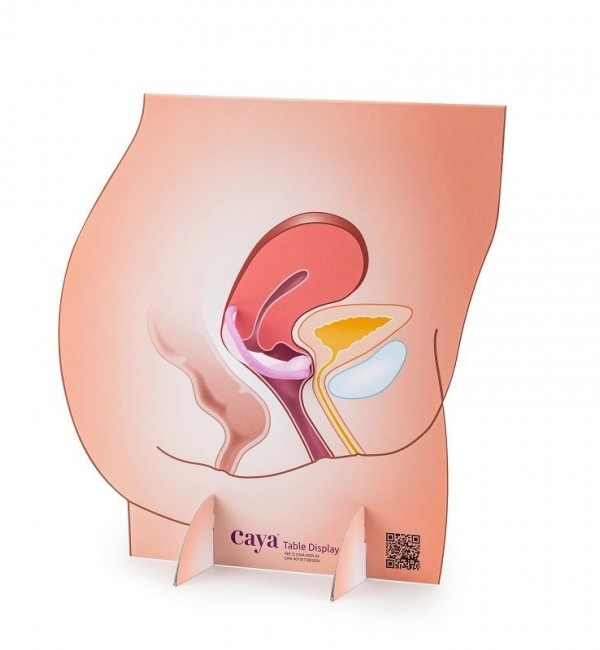

- Vaginismo

- Dopo interventi chirurgici ginecologici (per es. interventi per prolasso o in caso di tumori)

- Dopo interventi di riduzione della vagina e formazione di cicatrici

- Vaginoplastica stretta (verginità) descritta come disturbo sessuale dall’interessata

Gli esercizi di dilatazione con il dilatatore Vagiwell sono opportuni anche quando le visite ginecologiche o l’uso di assorbenti interni sono molto dolorosi.